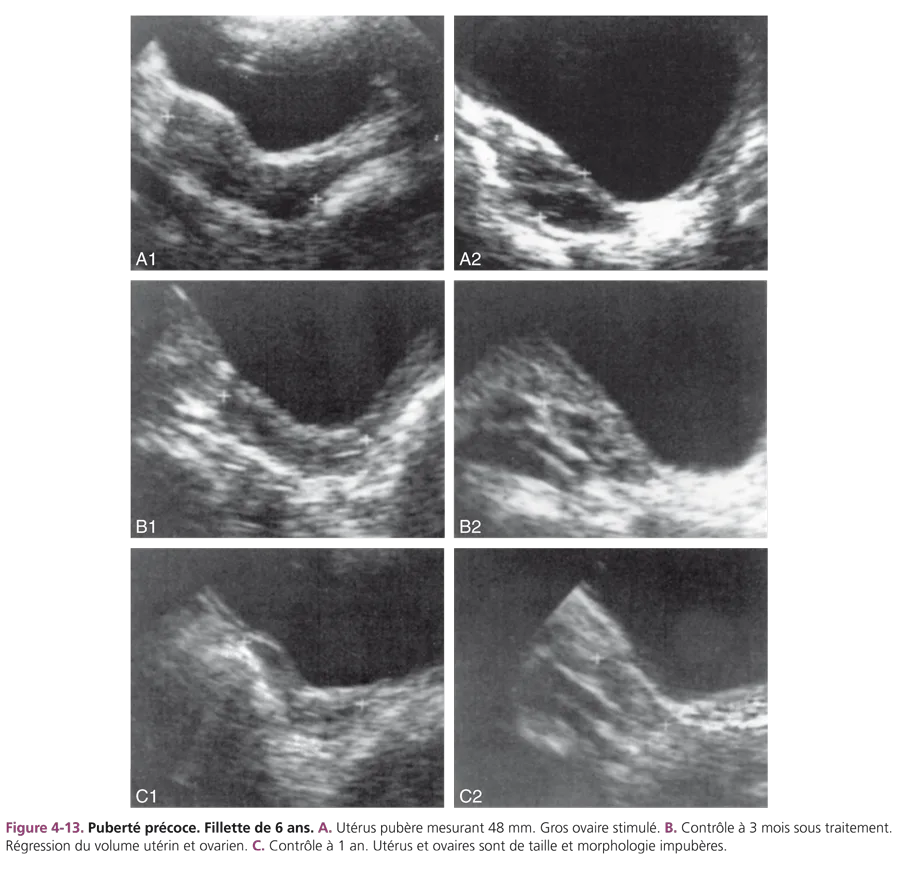

Le traitement de la puberté précoce idiopathique ou liée à un hamartome est médical, freinateur, par administration d’agonistes de la GnRH. Ce traitement, très efficace, entraîne une freination pubertaire prolongée, sans échappement [6]. L’échographie de surveillance, si elle est effectuée, constate la réduction du volume ovarien et l’absence d’activité folliculaire (fig. 4-13). La régression utérine est souvent partielle. À l’arrêt du traitement, le développement pubertaire s’effectue normalement.